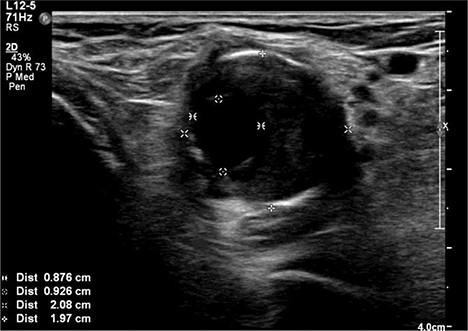

A 92-year-old female, independent from home, presented after multiple falls due to a four-month history of left foot drop. The foot drop had gradually worsened to the point that there was complete paralysis of ankle dorsiflexion and was associated with significant oedema of the foot. On examination, there was a large pulsatile mass in the popliteal fossa bilaterally. All peripheral pulses were palpable without any signs of ischemia. The most striking examination finding was complete paralysis of left ankle dorsiflexion with 0 out of 5 power. Ultrasound revealed that there were (Fig 1) bilateral popliteal artery aneurysms, which was larger on the left, causing displacement and impingement of the common peroneal nerve at the knee crease (Fig 2). Further computed tomography angiogram demonstrated an unruptured left PAA measuring 22 × 21 mm in maximal dimension over a distance of 24 mm (Fig 3). Intraluminal thrombus was also noted with 60% luminal stenosis. Distally, the arteries were heavily calcified with two-vessel runoff at the ankle. An emergency endovascular repair of the left PAA was performed by using 8 mm × 15 cm and 7 mm × 10 cm Gore Viabahn stents (Fig 4). The stents were deployed after a balloon-angioplasty and adequate decompression of the aneurysm was achieved. The postoperative period was uneventful, and patient’s pre-existing aspirin was continued. The leg and foot oedema improved rapidly over the subsequent few days. At follow-up in 12 weeks, the patient showed some return of motor function of the ankle and was walking with ankle splint. Her left leg remained well perfused with palpable pulses.

Computed topography angiogram image of left popliteal artery aneurysm, measuring 21 × 22 mm (AP × RL).